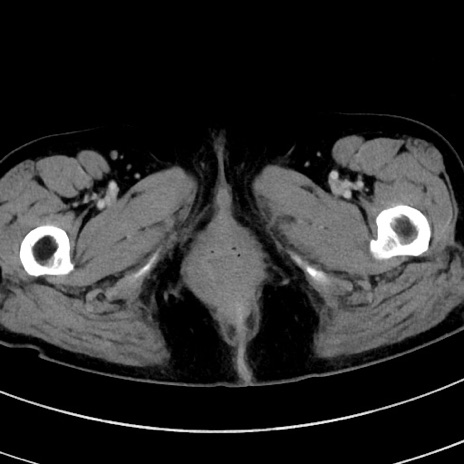

症例9(横断像)

【症例】 60歳代女性

【主訴】むかつき、みぞおちの痛み

【現病歴】3日前よりむかつきがあり、食事がとれない。

【既往歴】糖尿病

【身体所見】発熱なし、心窩部圧痛軽度あるも、腹膜刺激症状なし。

【データ】WBC 7400、CRP 1.92